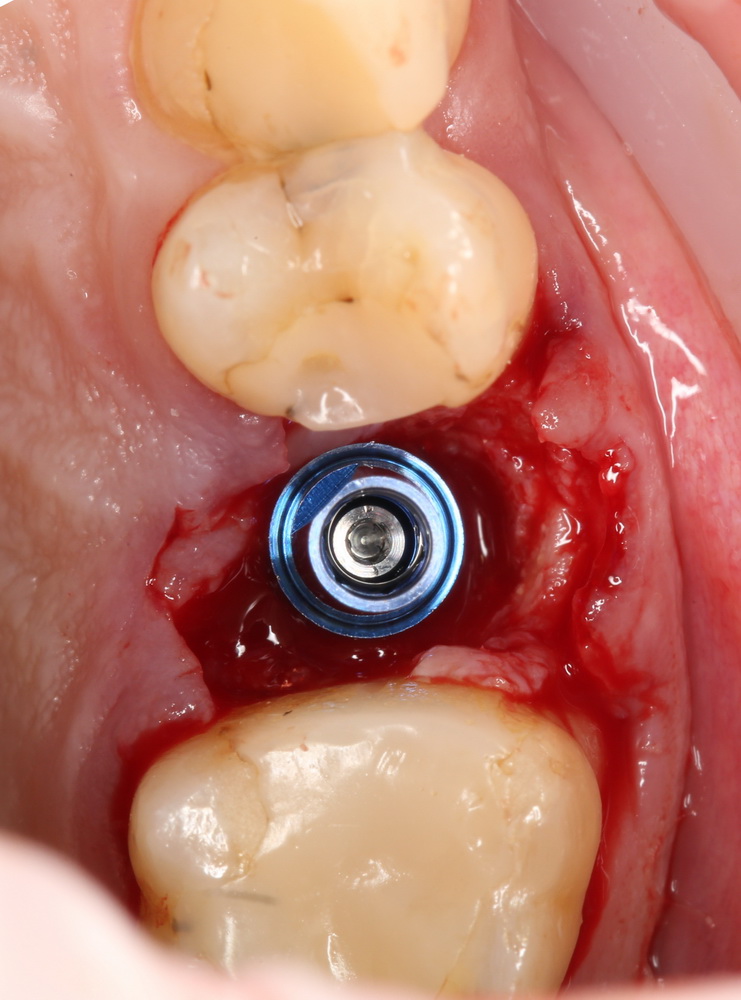

Установка имплантатов

По ряду уже упомянутых выше причин, для решения этой клинической задачи мы выбрали имплантаты Xive. Лунки для них мы уже приготовили. возможную первичную стабильность оценили. Имплантаты мы установили с усилием чуть больше 15-20 Нсм — такого крутящего момента более, чем достаточно, особенно если учесть, что временные коронки будут соединяться между собой.

Подробно о том, что такое крутящий момент и хирургический протокол можно прочитать здесь>> и тут>>, соответственно. Из-за использования специальных индивидуализируемых временных абатментов, имеющих только три положения, нам нужно позиционировать платформу имплантатов по граням. Это очень просто  — мы выводим вырез абатмента TempBase (он входит в комплект поставки) вестибулярно.

После перкуторной проверки стабильности имплантатов и точности позиционирования, мы переходим к следующему этапу — сохранению десневого контура.

Установка имплантатов занимает около двух минут.